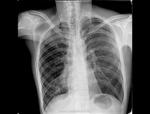

И представляю R контроль после выписки из ОПТД

Интересно, а сколько длилось лечения в ОПТД до контроля.

Лечение продолжалось 8 месяцев. Есть еще ФОГК контроль и после лечения.